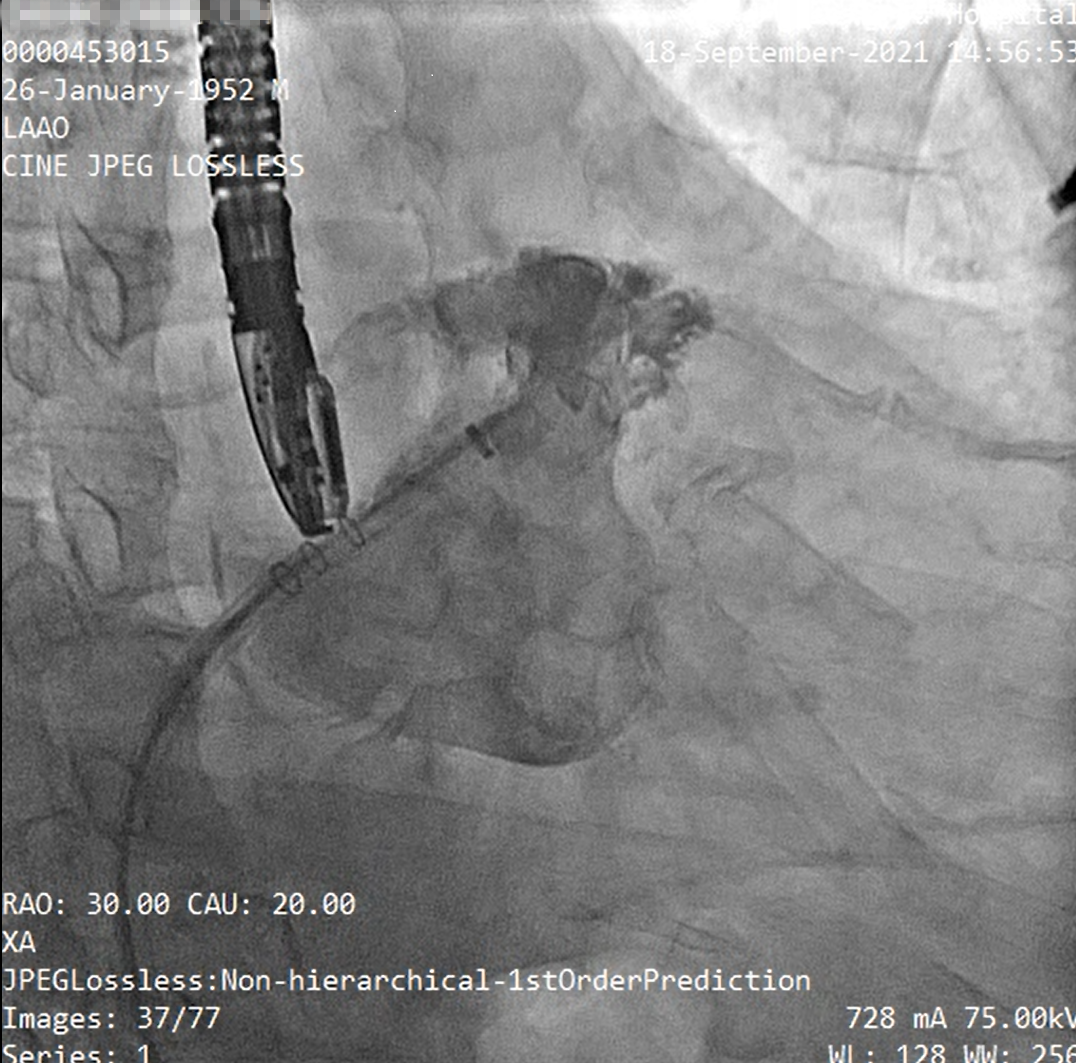

2021年9月18日成功置入澳门特别行政区首例WATCHMAN FLX左心耳封堵器

食道超声及左心耳造影

释放左心耳封堵器呈〝FLX BALL〞

经造影及食道超声检查后释放WATCHMAN FLX左心耳封堵器